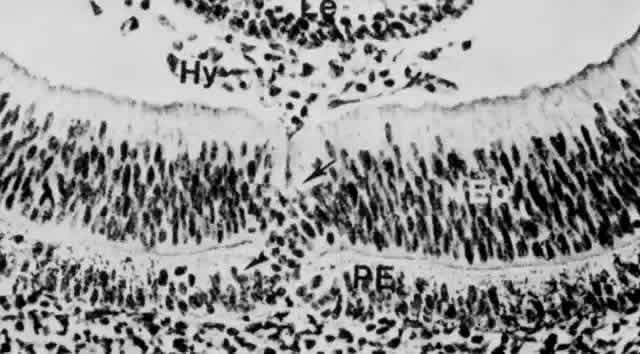

Fig. 9. Invagination of the optic cup and lens vesicle. Mouse embryos are illustrated. A. Embryo of somite pairs (fifth week in a human). On external examination, the invaginating lens placode can be seen (arrow). Note its position relative to the maxillary (Mx) and mandibular (Mn) prominences of the first visceral arch (× 106). B. Embryo of the same age as in Figure 3A. Frontal fracture through the lens placode (arrow) illustrates the associated thickening of the surface ectoderm (E). Mesenchyme (M) of neural crest origin is present adjacent to the lens placode. Distal portion of the optic vesicle thickens concurrently, as the precursor of the neural retina (NR), whereas the proximal optic vesicle becomes a shorter, cuboidal layer that is the anlage of the retinal pigmented epithelium (PE). The cavity of the optic vesicle (V) becomes progressively smaller (× 367). C. Epithelium of the lens placode continues to invaginate (L). There is an abrupt transition between the thicker epithelium of the placode and the adjacent surface ectoderm, which is not unlike the transition between the future neural retina (NR) and the future pigmented epithelium (PE). (Periodic acid-Schiff's stain; × 443) D. As the lens vesicle enlarges during the eleventh day, the external opening, or lens pore (arrow), becomes progressively smaller. The lens epithelial cells at the posterior pole of the lens elongate to form the primary lens fibers (L). NR, anlage of the neural retina; PE, the anlage of the pigmented epithelium (now a very short cuboidal layer) (× 300). E. External view of the lens pore (arrow) and its relationship to the maxillary prominence (Mx)—32 somite pairs (× 260). F. Frontal fracture reveals the optic fissure (*) where the two sides of the invaginating optic cup meet. This forms an opening in the cup allowing access to the hyaloid artery (H), which ramifies around the invaginating lens vesicle (L). The former cavity of the optic vesicle is obliterated except in the marginal sinus (S), at the transition between the neural retina (NR) and the pigmented epithelium. E, surface ectoderm (× 307).

The primordium of the retina is present at the optic pit stage early during the third week of gestation even before closure of the neural tube (see Fig. 4A and B). The anterior part of the optic vesicle, the retinal disc, is the future neural retina, and has a marginal nonnucleated layer in contact with the lens placode. The sides of the invaginating vesicle are destined to become the pigment epithelium (see Fig. 9C and D).

Following vesicle invagination to form the optic cup, the inner layer has an outer nuclear zone and an inner anuclear marginal zone. The outermost layer of cells of the nuclear zone (the germinating, or proliferative layer) projects cilia to the surface of the contacting outer layer, or future pigment epithelium. These cilia disappear during the seventh week. They are replaced by the precursors of the photoreceptor outer segments during the fourth month.

The outer layer of the cup has two to three layers of pseudostratified columnar cells that enclose pigment granules at 33 days' gestation (7 to 9 mm). This layer produces the earliest pigmentation in the body. Punctate tight junctions near their apical ends join the cells. The basal lamina that originally surrounded the optic vesicle remains continuous over the inner (vitreal) and outer surfaces of the optic cup.

The primitive retinal cells rest on a basement membrane that faces the inner future vitreal aspect and extend their apices toward the pigmented epithelial cells. In general, mitotic figures occur in the outer zone and prevail longest in the outer surface layer adjacent to the space representing the remnant of the primary optic cavity; and at the margin of the optic cup (future ciliary body-iris region). Mitosis first ceases in the central area; growth goes on longer in the periphery. Most cell division in the presumptive retina occurs before 120 mm (approximately 15 weeks). It is not established when mitosis ceases in the pigment epithelium. It is probably limited to the periphery in late fetal life.

Formation of Layers

Retinal differentiation commences when mitosis has practically stopped. It spreads from areas facing the future vitreous (marginal zone) toward the primary optic cavity, and from the center of the base of the optic cup (inner neuroblastic layer) toward its edge.159 Retinal ganglion cells and Müller's cells generally develop almost simultaneously. Here also, however, a gradient exists, given that axons and dendrites of ganglion cells near the optic nervehead differentiate earlier than those situated at the periphery. By proliferation and migration of cells, the neural epithelium separates into inner and outer neuroblastic layers in the seventh week of gestation (13 to 17 mm; see Fig. 11E and F). A few days later, a definite narrow nerve fiber layer is established, occasionally traversed by the radial fibers of the Müller cells.

Immature ganglion cell bodies move into the inner neuroblastic layer along with other less mature cells, presumably future amacrines, creating in their wake a nuclei-free entanglement of processes, the transient fiber layer of Chievitz (Figs. 29A and 30A). With further realignment of cells, this layer is mostly obliterated by 8 to 10 weeks' gestation. At this period, the cells of the inner and outer neuroblastic layers intermingle by means of their cytoplasmic extensions. They fill up the previously acellular Chievitz layer; cell bodies shift positions, establishing a new, comparatively cell-free zone of intertwined processes, the inner plexiform layer (50 to 55 mm, approximately 10.5 weeks) (see Figs. 29B and 30B). With the emergence of the inner plexiform layer, an inner nucleated layer, consisting mostly of the cell bodies of ganglion cells, becomes separated from an outer neuroblastic zone. The cell bodies of the Müller's cells and the developing amacrines are located near the inner border of the outer neuroblastic zone. Bipolar cells differentiate mostly from the middle portion of this outer zone, whereas horizontal cells and photoreceptors arise from its outermost region (see Fig. 29B and C, and Fig. 30B and C). These developmental processes are well under way by 10 weeks to 12 weeks (approximately 60 to 80 mm), when an identifiable outer plexiform layer separates the immature horizontal and bipolar cell nuclei from those of the photoreceptors.